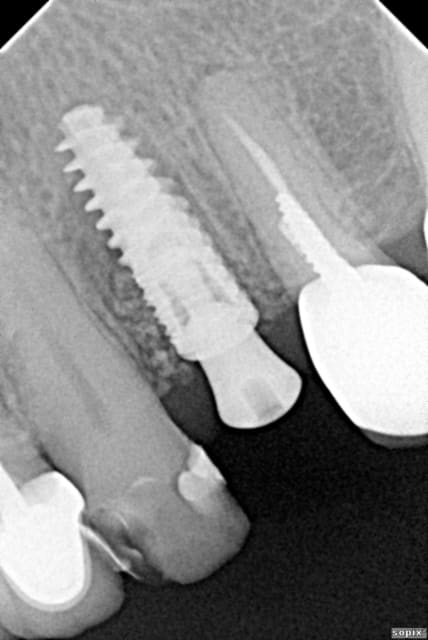

Un "vieux cas" LEONE qui se passe bien malgré des conditions de départ et de chirurgie pas au mieux! 4 ans déjà et aspect sympa très stable dans le temps. une de mes extractions implantation immédiate en site "pas idéal".La chronologie en rx.

Janvier 2008 vzunxr - Eugenol

Octobre 2008 ehmsfj - Eugenol

Mars 2008 jt5qx2 - Eugenol

Novembre 2011 ane4ar - Eugenol